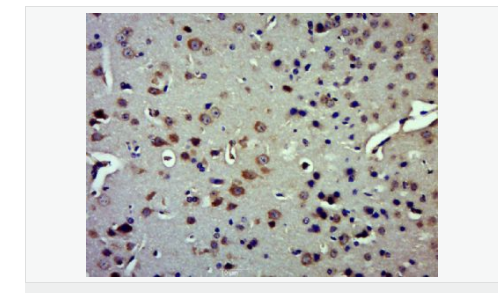

產(chǎn)品介紹Insulysin was identified nearly a century ago as an enzyme responsible for the degradation of insulin in cells, although the precise interactions between insulin and insulysin remain elusive. Human insulysin was cloned in 1988, and shown to be a 118 kDa protein that exists primarily as a homodimer, and perhaps also complexed with other molecules. The sequence is well conserved between humans, rats and mice, and the antibody recognizes these species. Insulysin is a metalloproteinase of the clan ME, family M16, which contains an active site HxxEH, a reversal of the canonical HExxH zinc binding motif. Considered a zinc metalloproteinase, the activity of insulysin can be blocked with EDTA or 1-10 phenanthroline. In addition to the active metalloproteinase domain, insulysin contains a second metalloproteinase site which is considered catalytically inactive, and is thought to assist in substrate binding. Insulysin is most closely related to the bacterial proteinase pitrilysin, (the human orthologue of which appears to be MPRP1) and the mammalian proteinsae nardilysin. Generally thought to be a cytoplasmic protein, insulysin has been isolated from many different tissues and cell lines, and can degrade intact insulin, insulin B chain, glucagon, denatured hemoglobin, alpha amyloid protein, TGF alpha and amylin. Recent work implicates insulysin in clearing beta amyloid plaques from the brain, and has generated much interest in Alzheimer’s disease research. The pH optimum for insulysin is basic, pH 8.5, which also distinguishes it from other metalloproteinases.

Plays a role in the cellular breakdown of insulin, IAPP, glucagon, bradykinin, kallidin and other peptides, and thereby plays a role in intercellular peptide signaling. Degrades amyloid formed by APP and IAPP. May play a role in the degradation and clearance of naturally secreted amyloid beta-protein by neurons and microglia.

Cytoplasm. Cell membrane. Secreted. Note=Present at the cell surface of neuron cells. The membrane-associated isoform is approximately 5 kDa larger than the known cytosolic isoform.